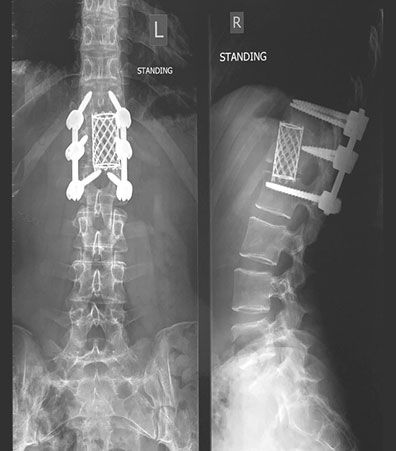

Следующие две недели я пролежала пластом на больничной койке в ожидании операции на позвоночнике. Будучи не в силах заснуть, продолжала мысленно рисовать картину того, что мне предстояло перенести. В это было невозможно поверить: хирург собирался вскрыть мое туловище, сначала сбоку, на уровне талии, а затем сзади, на уровне разрушенного позвонка. Он планировал извлечь костные фрагменты вместе с двумя соседними дисками, а потом соединить три позвонка вместе и скрепить позвоночник шестью металлическими стержнями длиной 7,5 сантиметра. Отверстия для них нужно было просверлить электродрелью.

Конечный результат. (Нет, рамка металлоискателя в аэропорту не звенит, и да, эти стержни останутся во мне навсегда.)